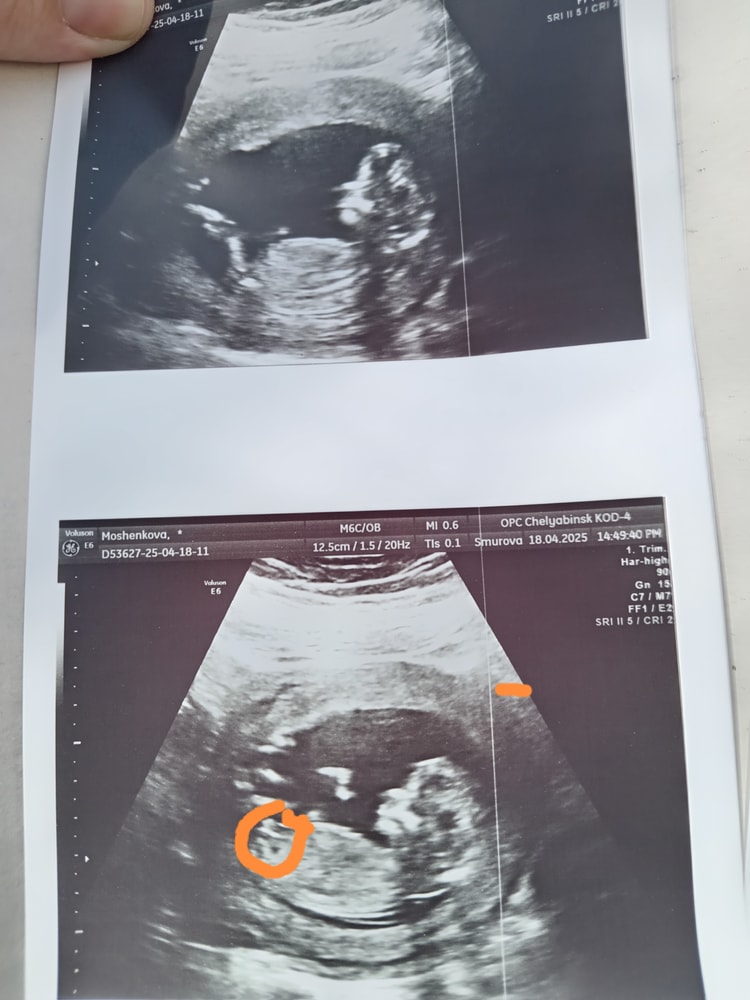

Оксана Мощенкова в Клуб беременных 8 месяцев Половой бугорок Пол малыша Девочки привет, как вы думаете кто будет, я что-то не пойму где тут половой бугорок😵💫😁 Посмотрите еще 20 записей на эту тему Отменить Ответить Елена Ивановская Вы узнали, кто у вас в итоге?) 16.05.2025 Ответить Оксана Мощенкова Елена Ивановская, нет ещё 16.05.2025 Ответить Мама дочи Плохо видно. Скорее всего девочка 20.04.2025 Ответить Юлянка Мальчик 20.04.2025 Ответить Оксана Мощенкова Юлянка, я поняла, что это половой бугорок 20.04.2025 Ответить Nika Какой носатенький мальчик😍 20.04.2025 Ответить Оксана Мощенкова Nika, это половой бугорок 20.04.2025 Ответить Оксана Мощенкова Оксана Мощенкова, 20.04.2025 Ответить Nika Оксана Мощенкова, я поняла))) 20.04.2025 Ответить Помогите определить пол ребёнка Пол малыша Чаты Беременных Выберите чат: Январята-2026 Февралята-2026 Мартята-2026 Апрелята-2026 Майчата-2026 Июнята-2026 Июлята-2026 Августята-2026